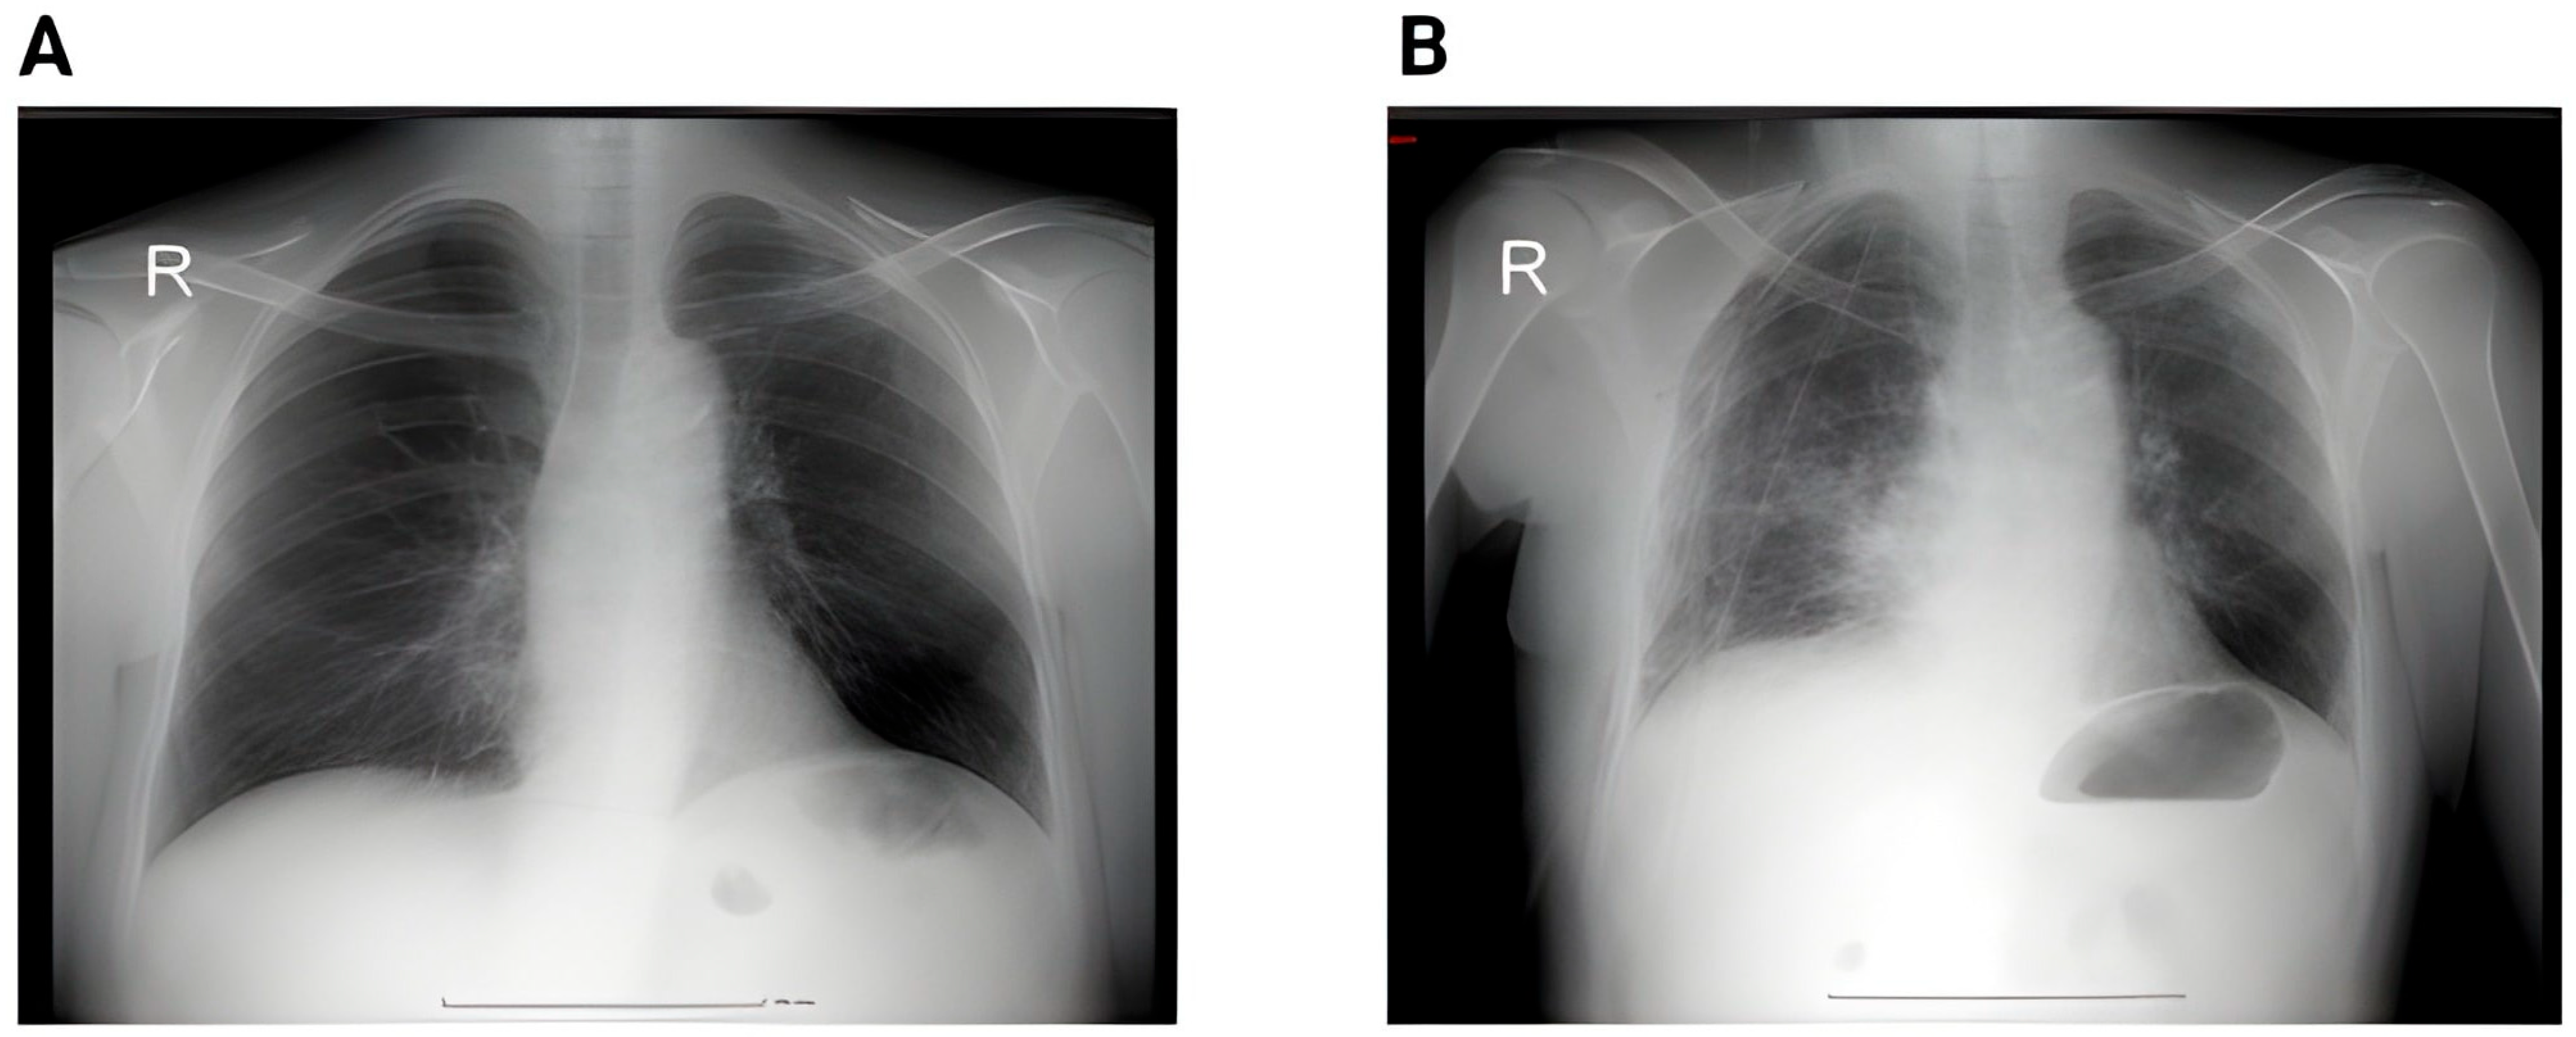

In contrast, the postoperative group demonstrates a clear reduction in both the number and variability of findings, with a lower median and compressed IQR, indicating clinical and radiologic improvement after surgery. Figure 2 shows the proportion of patients and the imaging changes.

To better illustrate the evolution of thoracic imaging findings in relation to surgical intervention, we compared the distribution of radiological abnormalities before and after pulmonary lobectomy. Figure 3 presents the boxplot analysis, highlighting the relative frequency of emphysema, atelectasis, pleural effusion, ground-glass infiltrates, and metastatic nodules.

To further explore the dynamic shifts in radiological findings following surgical intervention, we employed a bubble plot to compare preoperative and postoperative imaging features. As illustrated in Figure 4, each bubble represents the relative proportion of patients exhibiting specific abnormalities, with size corresponding to frequency.

Emphysema (29.6%), pleural effusion (12.8%), and atelectasis/pleural thickening (15.2%) were frequent before surgery but decreased following, as shown by decreasing bubble sizes. Despite a lower preoperative Y-axis position, the proportion of patients with no imaging abnormalities improved postoperatively to 24.8%, displayed by a larger red square.